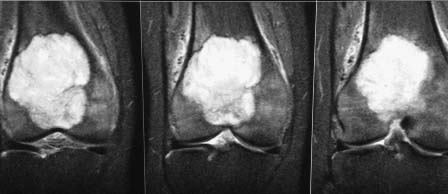

Помогите определиться с дальнейшей тактикой у молодой женщины с опухолью дистального отдела бедра. Обратилась на консультацию молодая женщина 34 лет. В январе появились боль в правом коленном суставе. Амбулаторно р- гр в прямой проекции - норма. Была незначительная травма. Боль усилилась. На днях повторно обратилась в поликлинику на рентгенограммах выявлена опухоль дистального метаэпифиза бедренгой кости. Сделано мрт. Мягкотканного компонента нет. Суставной хрящ пока интактен. Рентгенограмм прилагается. Завтра выложу мрт и сделаем ркт ( то же выложу) Предполагаю, что это остеобластокластома. Биопсию не сделаем, кт с контрастом и сцинтиграфию тоже. Учитывая угрозу патологического перелома рекомендовал костыли.

прилагаю МРТ и КТ. Образование накапливает радифармпрепарат :(

Снимки

Внешне похоже на ОБК. Другой вариант - аневризмальная киста, но вряд ли (на МРТ обычно видны множественные уровни жидкости).